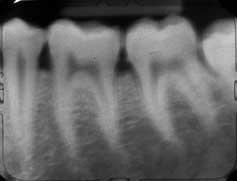

La imagen de arriba muestra los resultados de una angulación vertical incorrecta de la película, lo que resulta en la elongación de las raíces y la visualización inferior del borde de la mandíbula.